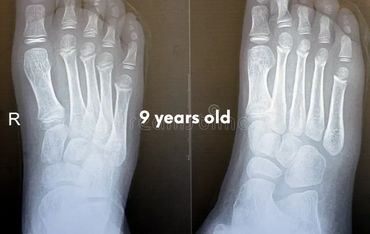

Let's check what their foot bones look like.

Pictures below will let you understand how babies' feet are developed.

Dear parents, children’s feet are developing structures, and the absence of an arch is a typical stage of development. The developing foot is not structurally ‘flat’; it is a highly compliant and plastic, that can respond to multiple factors, many of which we do not understand. Detailed X-RAY pictures above, let us understand that babies' foot bones are not connected till the teen years. Only at the age of 14, we may consider that the bones in the feet are developed and have reached their connections.